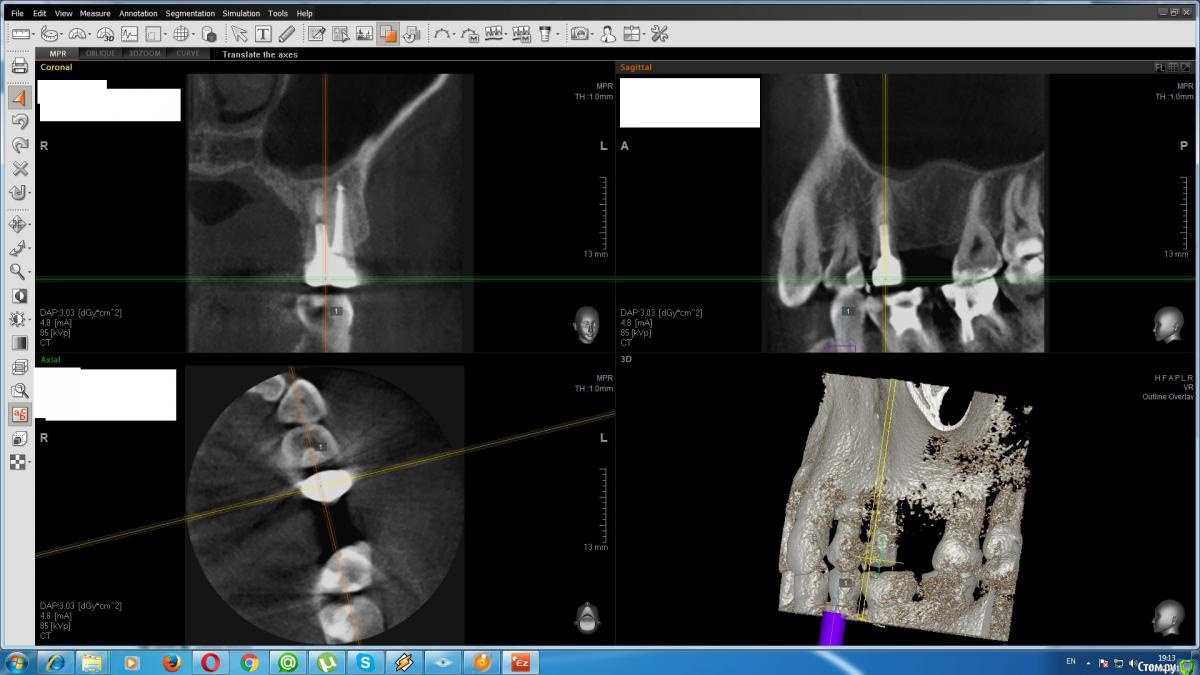

duss1981 Опубликовано 3 февраля, 2017 Поделиться Опубликовано 3 февраля, 2017 (изменено) Добрый день. год назад лечили 5 зуб, запломбировали. Сейчас сделали 3D снимок соседнего 6го для протезирования. Смотрю вроде на 5ке не до конца 1 канал запломбирован или это дефект съемки? Заранее благодарен Изменено 3 февраля, 2017 пользователем duss1981 Ссылка на комментарий

St. Опубликовано 3 февраля, 2017 Поделиться Опубликовано 3 февраля, 2017 По приложенному снимку все прилично. 1 Ссылка на комментарий